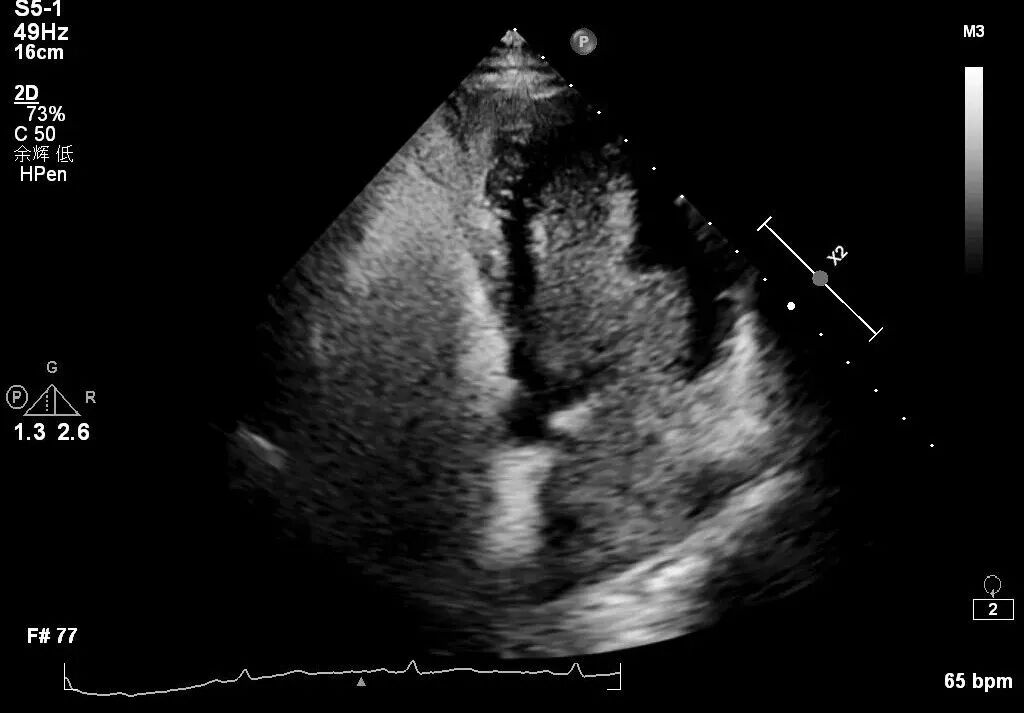

这不仅困扰着患者与家属,也成为摆在医生面前的难题。常规经胸心超提示,患者心脏房间隔可能存在一个极细微的“卵圆孔未闭”。然而图像朦胧,难以定论。这是一个隐蔽的“心眼”,却可能是血栓潜入大脑的通道。若不能证实,患者将面临复发风险;若不能精准评估,治疗便无从谈起。

经胸心超